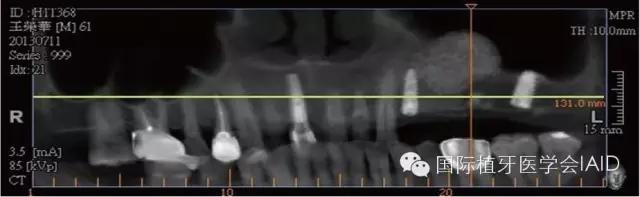

在植牙手術(shù)執(zhí)行之前,需要進(jìn)行全口檢查與軟硬組織的評(píng)估??谕馐嗄P团ccone beam CT資料搜集有助于治療計(jì)劃的擬定。在石膏模型上進(jìn)行diagnostic wax up有助于決定植體上假牙前后關(guān)系、頰舌側(cè)位置、咬合高度、及植體與植體上假牙的高度比例。使用Cone beam CT(CBCT)可以容易了解手術(shù)區(qū)硬組織條件,如Septum、骨頭高度及寬度、骨頭密度、神經(jīng)血管位置等。分析以上數(shù)據(jù)后,較容易得到可預(yù)期性的結(jié)果。

初期穩(wěn)定度在第一及第二類型的案例(>9mm; 6mm-9mm) 可以較容易達(dá)到,故通常以crestal approach進(jìn)行手術(shù)。Lateral window術(shù)式在第三型(3mm-6mm)較被建議。 若是前三個(gè)類型的初期穩(wěn)定度達(dá)到35Mpa,可以考慮當(dāng)次放置植體。若骨頭條件屬于第四型(<3mm),Lateral approach 比較建議使用,而植體可考慮等到Grafted Bone較成熟時(shí)再置入。(Fig. 1 & 2)術(shù)式的選擇與骨頭高度有密切的關(guān)系,當(dāng)骨頭垂直高度小于3 mm(于兩顆植體中),植體應(yīng)考慮 Bone graft穩(wěn)定后再植入。